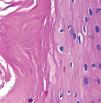

El estudio histopatológico mostró una lesión crateriforme, bien delimitada, con el centro ocupado por material queratósico que comunicaba con la superficie externa de la piel y la base constituida por un epitelio escamoso hiperplásico donde se evidenciaba queratinización tricolémica (fig. 2). El epitelio estaba constituido por una primera capa periférica de células cuboideas, dispuestas en empalizada, que se asentaban sobre una membrana basal y varias capas suprayacentes constituidas por células escamosas grandes, de citoplasma amplio y pálido (fig. 3), que queratinizaban de forma abrupta, sin mediar capa granulosa previa y dando lugar a una queratina eosinófila, compacta y ortoqueratósica (fig. 4). En la base del tumor se podían observar pequeñas estructuras que recordaban a quistes tricolémicos en miniatura. Se estableció el diagnóstico de cuerno tricolémico o queratosis tricolemal.

Detalle de la figura 3. Queratinización sin capa granulosa, dando lugar a una queratina compacta, eosinófila y ortoqueratósica. Eosina-hematoxilina, x200.